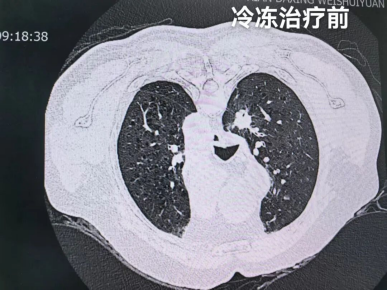

治疗流程按预设方案有序推进:第一步为CT引导精准定位,在影像科团队的协助下,医生借助CT影像系统清晰标定左肺结节的三维坐标,精准锁定病灶范围,为后续操作建立精准导航。

定位完成后,立即开展第二步穿刺活检术,医生沿定位路径实施经皮穿刺,成功获取结节组织样本后,即刻送检病理科进行快速现场评估(ROSE检测)。

这种检测能快速明确病变性质,仅耗时10分钟便出具病理报告。病理科医生随即向李大爷及家属告知结果:“确诊为非小细胞肺癌,目前病情符合冷冻治疗指征,即刻启动下一步治疗。”

第三步微创冷冻消融治疗随即开展。治疗采用三循环冷冻-复温模式:先通过冷冻针释放低温使肿瘤组织形成冰球,覆盖整个病灶区域;首次冷冻结束后进行复温,随后重复两次冷冻-复温循环,以强化对肿瘤细胞的杀伤效果。

整个治疗过程耗时约1.5小时,顺利完成。术后即时影像检查显示,肿瘤病灶已被冰球完整覆盖,消融效果达到预期。